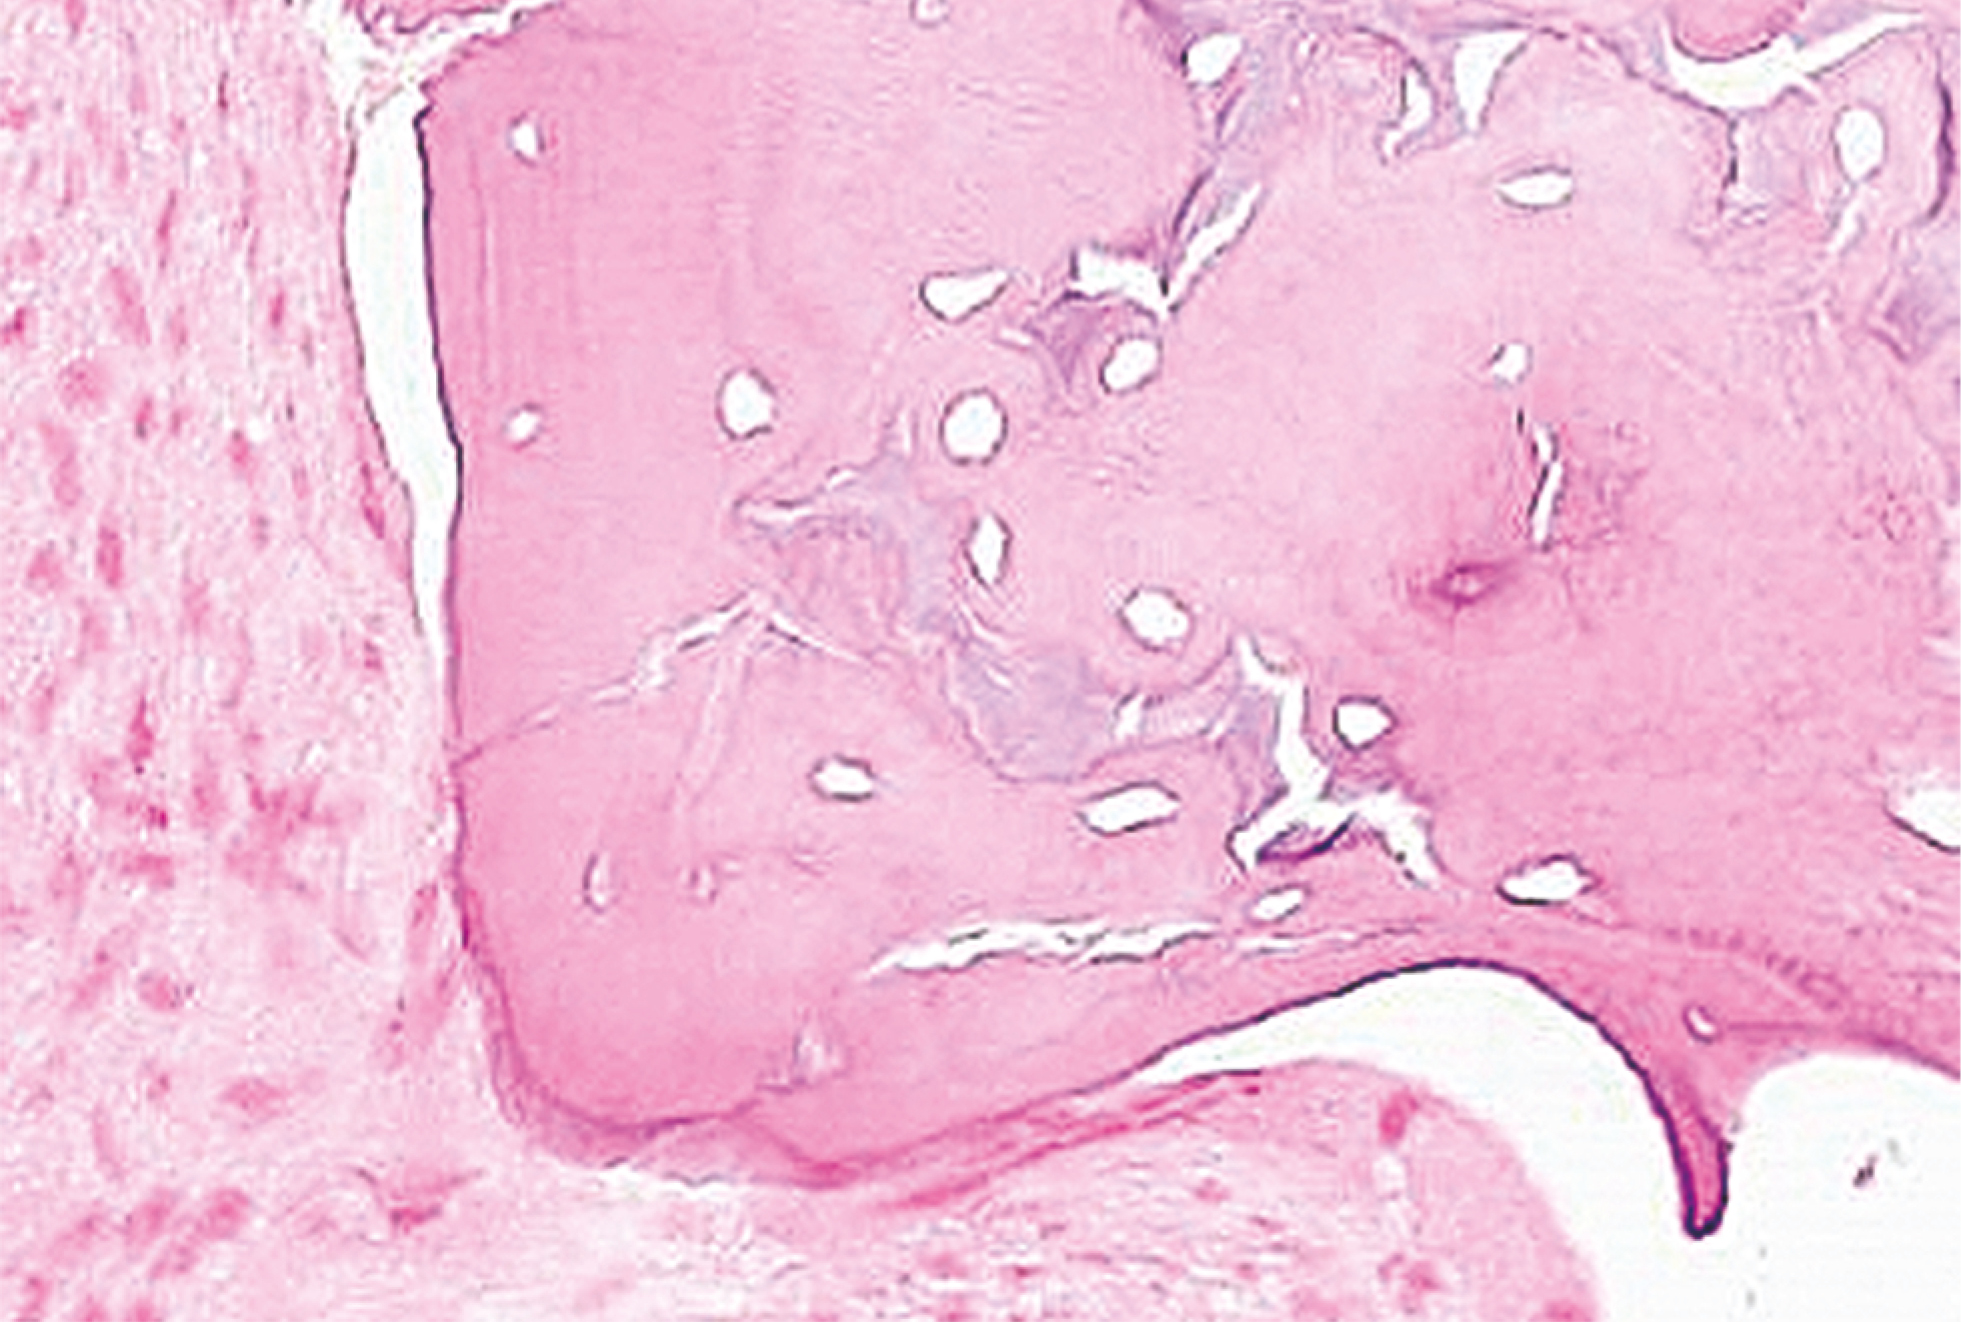

По данным гистологического исследования отмечается преобладание зрелой ламеллярной кости с активными остеобластами и преостеобластами, многоядерные остеокласты ещё обнаруживаются на границах остатков материала (рис. 2).

Рис. 2. Новообразованная костная ткань после применения комбинации костнопластических материалов «Остеоматрикс», «Биоимплант ГАП», «Биоматрикс». Окраска гематоксилином и эозином